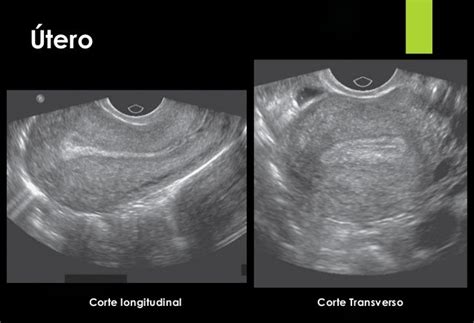

Ecografía Transvaginal

La ecografía transvaginal es una prueba fundamental en el estudio de fertilidad femenina. Permite una visualización detallada del útero y los ovarios con dos objetivos principales:

- Comprobar la existencia de malformaciones uterinas u otras anomalías anatómicas.

- Realizar un recuento de folículos antrales (RFA) para valorar la reserva ovárica, idealmente en los primeros días del ciclo menstrual.

Durante la prueba, el ginecólogo introduce una sonda ecográfica cubierta por un preservativo y lubricada con gel a través de la vagina. Esta sonda emite ondas sonoras que, al rebotar en los órganos, generan imágenes en una pantalla. La paciente puede sentir una leve presión, pero la prueba es indolora.